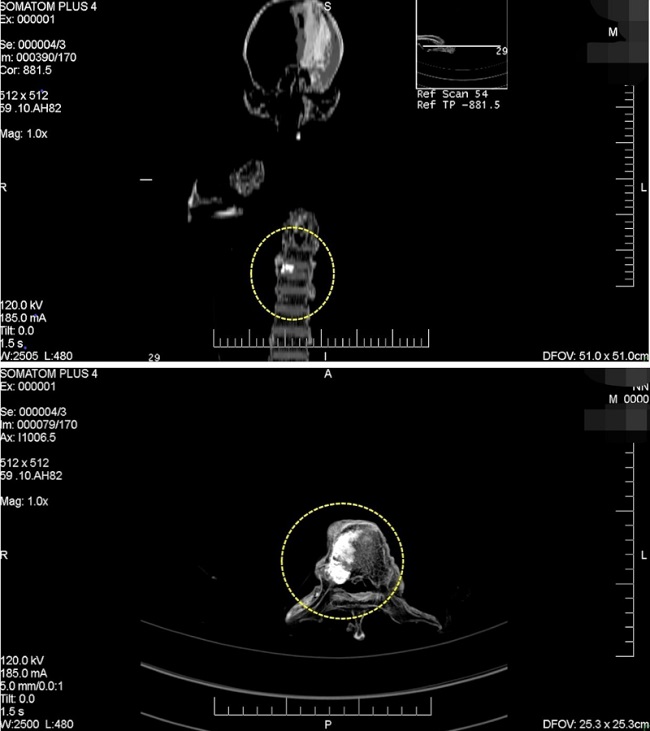

Posteriormente, y como resultado de la toma de radiografías y tomografías, se identificaron marcadores de cambios degenerativos en las articulaciones. Para la columna vertebral se detectó la presencia de lesiones osteoartríticas que incluyen osteofitosis y espondilosis en algunas vertebras torácicas, lumbares y el sacro. Asimismo, se observó en algunos cuerpos vertebrales torácicos signos de osteoporosis (pérdida de densidad ósea) y adelgazamiento derivado en acuñamiento, así como una platispondilia traumática de la vértebra D8 (Fig. 7). Dentro del hueso esponjoso del cuerpo de la octava vértebra torácica, se detectó la presencia de un foco de crecimiento de hueso compacto maduro de pocos centímetros conocido como enostosis (Mann y Hunt, 2005; Fig. 8).

Con respecto a la enostosis o islote de condensación observada en la octava vertebra torácica, está conformado mayormente por hueso compacto normal y probablemente tenga el origen en una anomalía de desarrollo (Mann y Hunt, 2005). Aunque se manifiesta generalmente en el fémur, pueden hacerlo en cualquier hueso, principalmente, después de la pubertad, y raramente presentan actividad, salvo los de mayor tamaño (Delgado, 2003).

En relación a estas últimas patologías, se solicitó a la Secretaría actuante la entrega de estudios médicos antemortem. Como resultado de dicha diligencia, se pudo contar con una resonancia nuclear magnética que muestra aplastamiento vertebral por fractura patológica a nivel de la octava vértebra torácica. Además de esto, se realizó un centellograma óseo que mostró a nivel de la D8 hipercaptación del material radioactivo, a partir del cual se orientó la investigación a una identificación tentativa (Fig. 9).